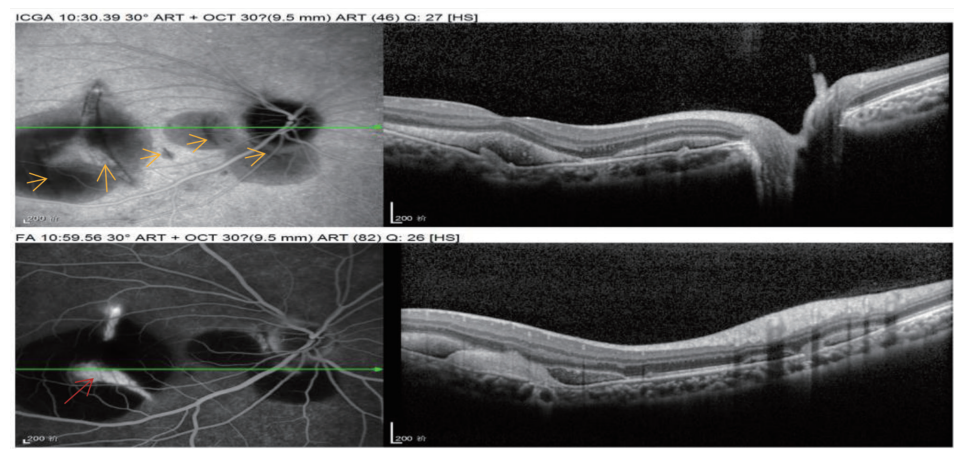

1 病例资料

患者,男, 16岁,体校学生,汉族,因“右眼眼前黑影遮挡,伴视力下降 2 周”为主诉入院。 2周前无明显诱因出现右眼眼前黑影遮挡,伴视力下降,不伴眼红、眼痛、畏光、流泪等症状。既往体健,生命征平稳,心肺腹未发现明显异常。眼部情况:右眼视力0.02, -3.00DS/ -1.25DC*171=0.25,左眼戴镜视力0.4, -1.75DS/ -1.50DC*9=1.0,双眼眼前节情况可,左眼眼底大致正常。右眼眼底及辅助检查(图1~6):黄斑区见一不连续弧形黄白色病灶,其周围见类圆形出血性神经上皮脱离(图1)。自发荧光显示黄斑区多个弧形呈低荧光病灶,黄斑去血性神经上皮脱离,部分因血自发荧光增强(图2)。行光学相干断层扫描血流成像(optical coherence tomography angiography,OCTA)检查,在视网膜无血管层可见弧形低密度区及网状CNV结构(图3),在脉络膜毛细血管层见经过黄斑中央脉络膜毛细血管弧形缺损区,暴露其下脉络膜中层血管(图4)。行荧光素钠造影(fluorescein angiography,FA)联合吲哚菁绿造影(indocyanine green angiography,ICGA)检查,ICGA见经过黄斑中心凹处一新月形弱荧光,视盘颞侧见多处小弧形弱荧光,均为脉络膜破裂部位。破裂病灶对应线扫光学相关断层扫描(optical coherence tomography,OCT)图RPE-Bruch膜复合体及脉络膜毛细血管断裂处,凹陷处见中高反射瘢痕信号,FA可见弧形染色并且中央有楔形荧光渗漏,考虑有脉络膜新生血管(choroidal neovascularization,CNV)形成可能(图5)。诊断:右眼多发性脉络膜破裂并CNV形成、黄斑视网膜下出血、双眼屈光不正。治疗上予玻璃体腔注射抗血管内皮生长因子(vascular endothelial growth factor,VEGF)治疗后1个月随访,视网膜下出血吸收,矫正视力提高到0.6(图6)。

20230131163947_0165.png

图5 ICGA对弧形病灶内强荧光显示得很清晰,视盘周围还可见好几处弧形病灶(黄色箭头),对应OCT见RPE及脉络膜毛细血管凹陷,凹陷处见中高反射瘢痕信号,FFA可见弧形染色并且中央有楔形荧光渗漏,考虑有CNV(红色箭头)

Figure 5 ICGA clearly showed strong fluorescence in curved lesions, and several curved lesions (yellow arrows) could be seen around the optic disc. Corresponding to OCT, there were RPE and choroidal capillary depressions, moderate and high reflection scar signals in depressions, arc staining in FFA and wedge-shaped fluorescence leakage in the center. CNV (red arrow) was considered